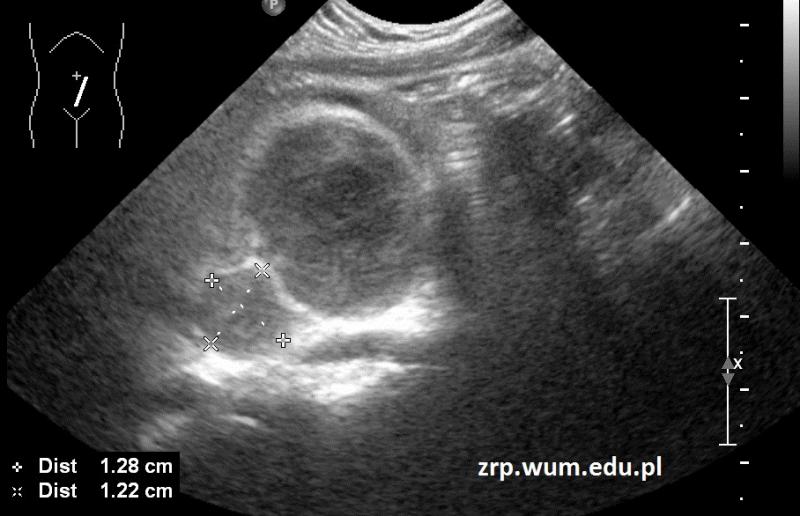

Przypadek 53: 4-letni pacjent obserwowany w kierunku choroby układowej, z obrzękiem i bólem kolana prawego, ze stanami podgorączkowymi utrzymującymi się od miesiąca.

Rozpoznanie: W badaniu USG w śródbrzuszu, pod pępkiem, uwidoczniono dwie hipoechogenne owalne zmiany, o wym. 37x27x22mm i 13x12mm, na tej podstawie wysunięto podejrzenie chłoniaka. Potwierdzono rozpoznanie chłoniaka Burkitta